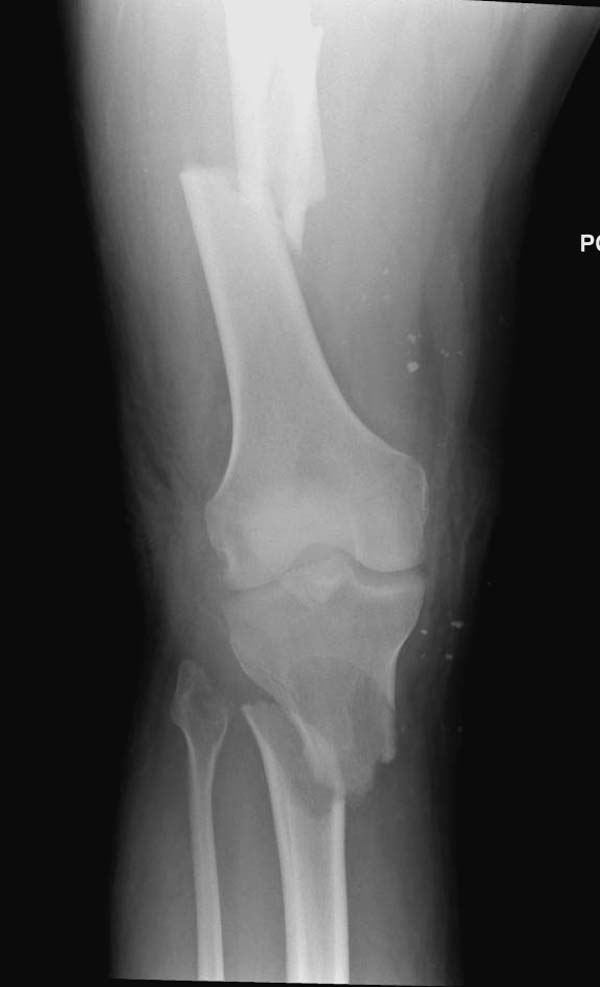

Здесь, кроме перелома верхней трети голени, имеется вовлечение сустава, и, чтобы не пропустить смещение суставной поверхности, надо делать КТ. Срезы КТ покажут о необходимости субхондральной фиксации, которая проводится 3.5 мм параллельными шурупами (Raft technique). Не имеет значения, как проводить: отдельно субхондрально или через верхний ряд пластины. Главная задача фиксации удержать суставную поверхность от коллапса в вальгус или варус.

Здесь случай, так называемого floating knee перелома выше и ниже коленного сустава.

Имя     : 4 Proximal tibia injury knee.JPG